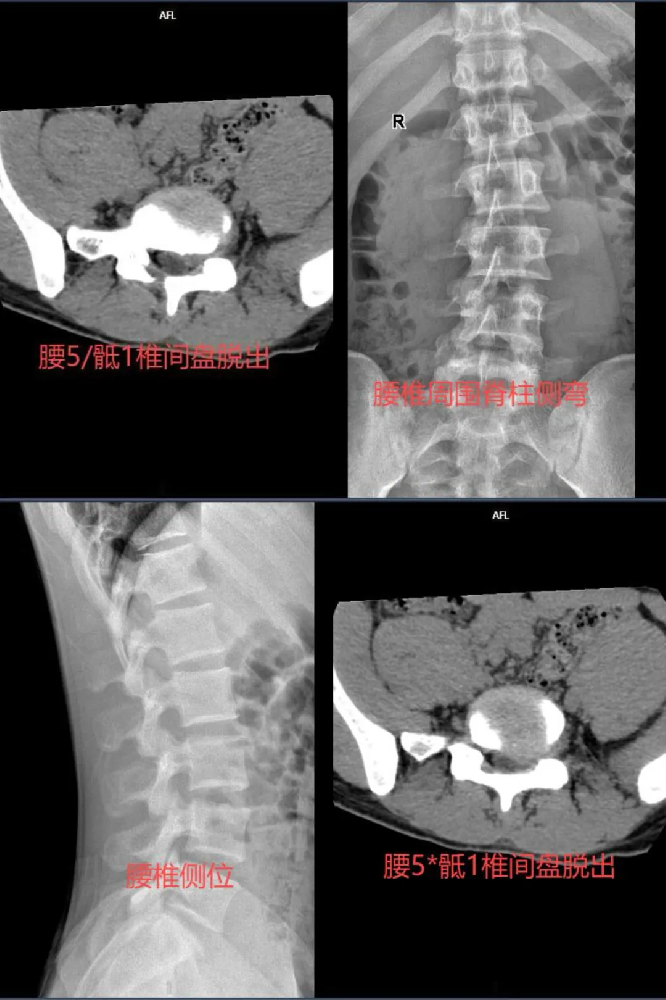

据了解,患者为男性、18岁,腰痛伴左侧臀部疼痛1年,曾多次住院腰椎牵针灸针刀熏蒸及药物治疗无效果。1年来病情呈加重趋势,平卧休息及翻身无明显腰臀部疼痛,坐位、站立及下肢腰及左侧臀部疼痛及明显加重,严重影响日常生活,腰椎磁共振检查提示腰5/骶1椎间盘脱出。

患者入院后,骨科医护团队积极完善相关检查,发现患者L5-S1间盘脱出到椎管及椎间孔压迫神经根。骨科医疗团队仔细分析病情、认真研究治疗方案,耐心细致与患者及家属沟通,讲解病情。经综合评价病情,患者非常年轻,骨科手术团队为患者制定了:内镜下后侧入路(腰5/骶1)单侧椎管扩大成形术+髓核摘除术+神经根松解术+纤维环缝合术,患者对骨科医疗团队服务态度及技术水平深信不疑。